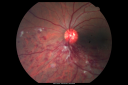

Optic Nerve Tumor913 viewsYoung male patient with a tumor present on the optic nerve in the right eye. VA is hand motion in the right eye